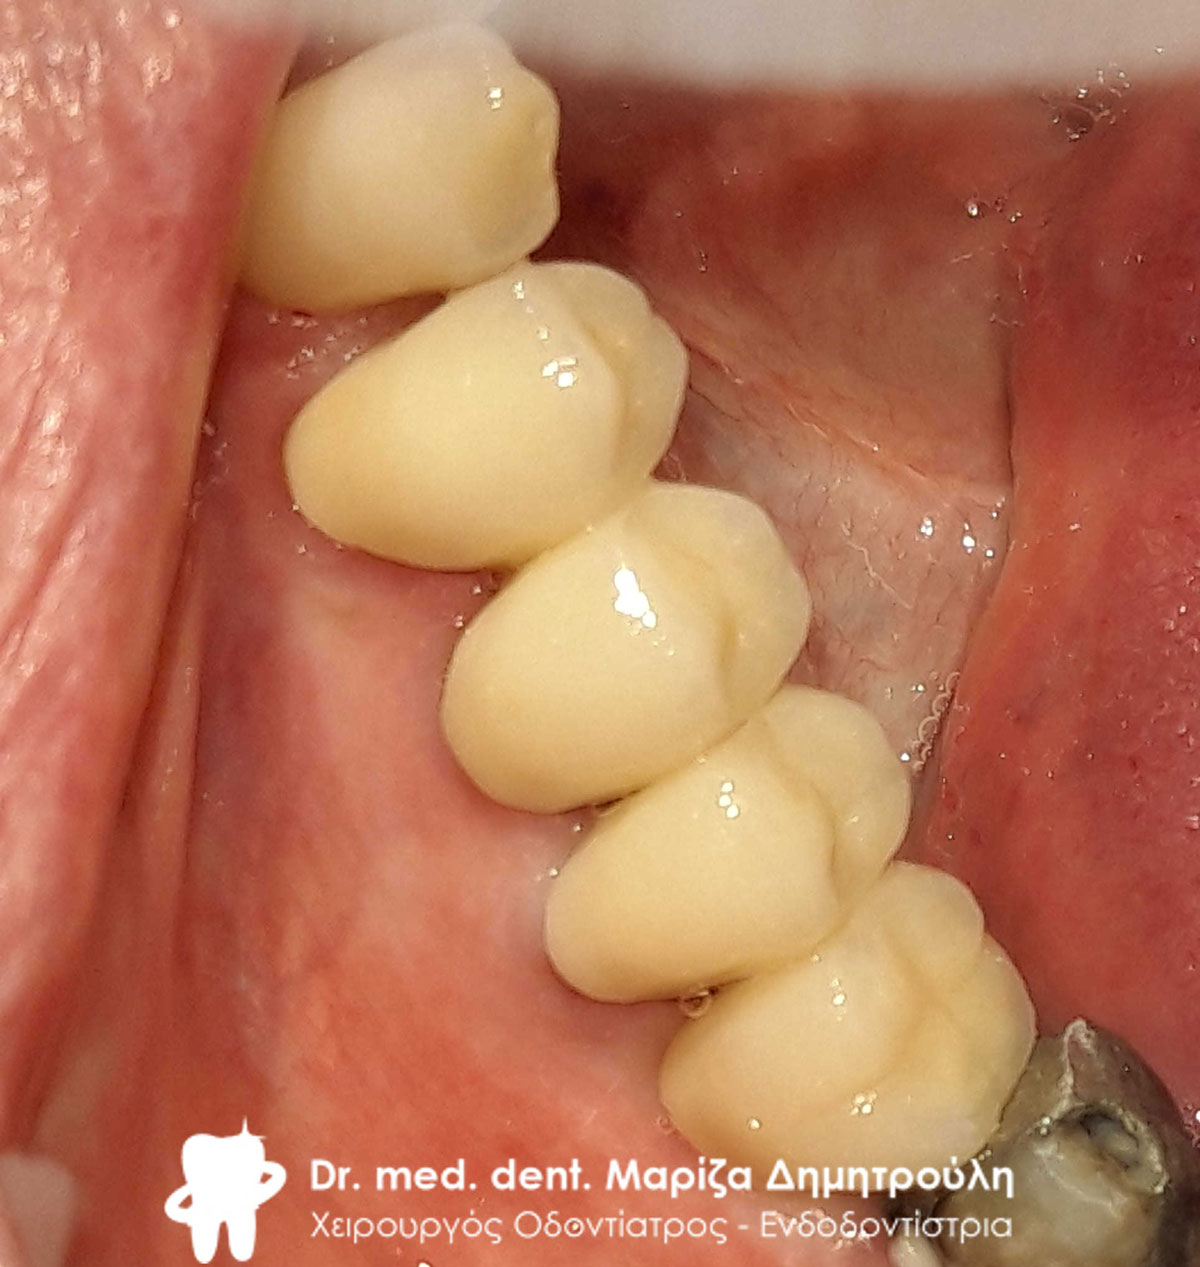

Τελική εικόνα του ολοκεραμικού πέταλου ζιρκονίου στην κάτω γνάθο

Τελική εικόνα του ολοκεραμικού πέταλου ζιρκονίου στην κάτω γνάθο